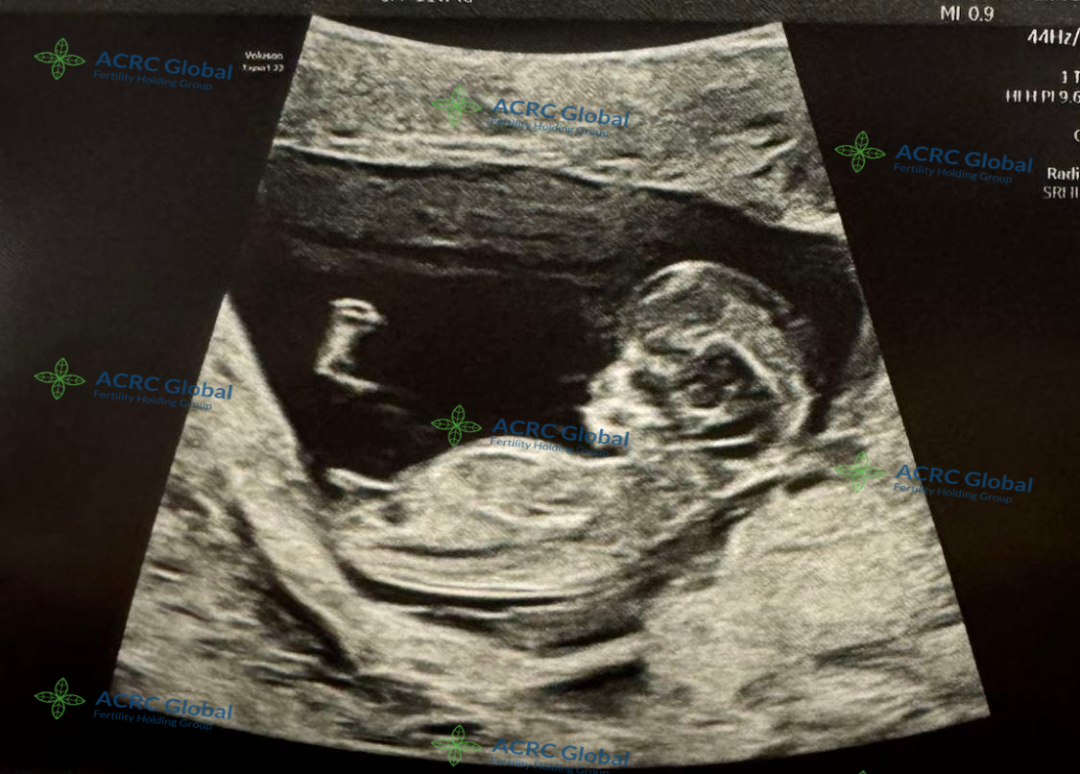

来自伊利诺伊州的爱妈C的第二次孕期旅程也进展顺利,胎宝宝已经进入11周阶段。在这个时候,宝宝已经完成了胚胎期的发育,进入胎儿期,逐渐变得更加稳定。

胎宝宝大约有5厘米长,体重约为7克左右

宝宝的器官和系统正在快速发育,心脏已经开始跳动,神经系统也在形成,B超显示宝宝的手指和脚趾已经开始分开,外耳、鼻子和嘴巴的结构也变得更加清晰。虽然胎宝宝还很小,但此时的他已经开始在羊水中轻微移动,只不过爱妈还感受不到这种活动。